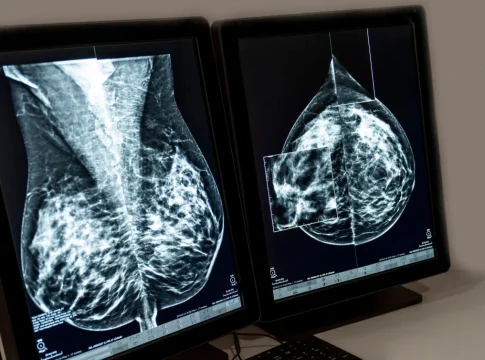

El cáncer de mama es el cáncer que se diagnostica con mayor frecuencia en Europa, y aproximadamente el 70% de los casos, en etapas tempranas de la enfermedad. A pesar de las opciones terapéuticas actuales, las personas diagnosticadas con cáncer de mama localizado HR+/HER2- en estadios II y III siguen corriendo el riesgo de que su cáncer reaparezca a largo plazo, a menudo como una enfermedad avanzada incurable.